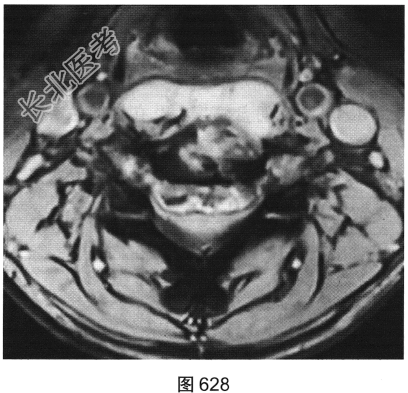

- [材料题] 患者男性,34岁,近数月乏力,偶有低热。颈部疼痛2个月余,逐渐加重,有轻压痛,颈部活动受限。

- 多项选择题2.[提示]患者行颈椎X线、CT和MRI检查,见图623~图628。首先应考虑患者为下列哪种疾病( )

A、淋巴瘤

B、骨髓瘤

C、颈椎退变

D、颈椎结核

E、化脓性颈椎炎

F、转移瘤